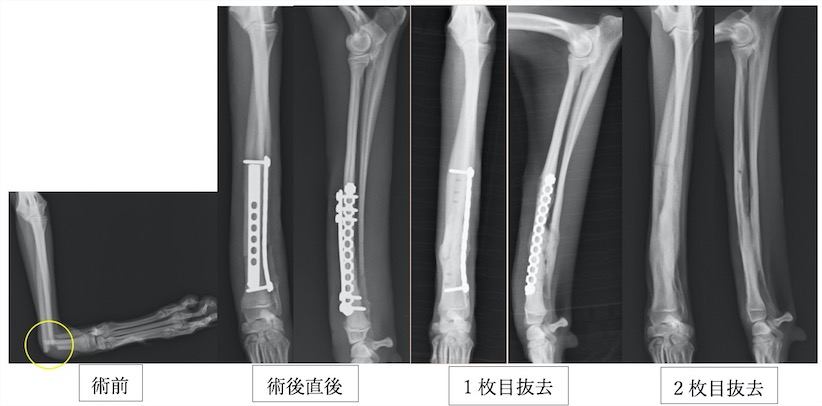

イタリアングレーハウンドの橈尺骨骨折です。2.0mmスクリューを使用しています。

上の3症例ともにやや中央寄りの先端部の橈尺骨の横骨折(遠位骨幹部橈尺骨横骨折)です。直線のプレートを使用しています。